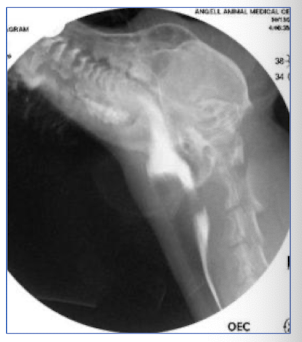

A persistent right fourth aortic arch is formed by what structures?

vascular ring of aorta, pulmonary artery, & ductus arteriosus

Dilation of the esophagus due to a persisent right fourth aortic arch occurs ________ to the heart.

cranial